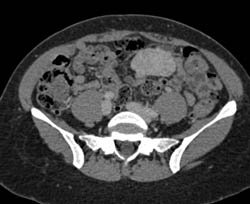

Diagnosis

Focal Nodular Hyperplasia (FNH)